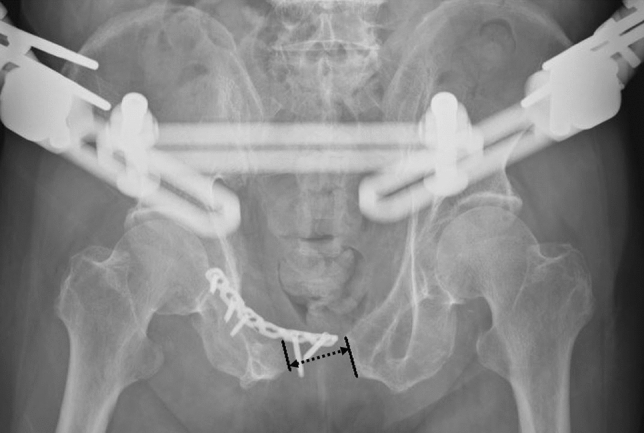

All injured pelvises were evaluated by radiography and computer tomography. The injured pelvises were classified according to the Young-Burgess Classification. After resuscitation and stabilization of the patient’s vital signs at the time of the initial injury, open reduction and internal fixations were carried out as early as the patient’s general condition allowed. The indication for plating of symphysis diastasis was anterior instability of the pelvic ring. Posterior fixation was additionally performed if posterior instability of the pelvic ring was present. The choice of a single or double plate for the symphysis plating depended on the surgeon’s preference. Rehabilitation interventions were started on the first day after surgery. The patients were encouraged to have early mobilization. Patients with anterior ring disruption alone were allowed partial weight bearing to 50% of their body weight after surgery. Patients with concomitant iliac wing or posterior ring injury were allowed toe-touch weight bearing on the side of hemi-pelvic injury and were allowed to walk on crutches for the first 6 weeks. Partial weight bearing to 50% of the bodyweight was followed during the next 6 weeks. Full weight bearing, as tolerated, commenced 3 months postoperatively. Radiographs of the pelvis anteroposterior (AP) view were obtained at the time of initial injury; immediately postoperatively; and at the 3-, 6-, and 12-month follow-ups. The pubic symphysis distance (PSD) was measured as the narrowest distance between the bilateral pubic ramus on the patients’ radiographs and was recorded (Fig. 1).

Fig. 1.

Implant failure with loss of reduction, showing a pubic symphysis distance (arrow dotted line) over 2.5 cm

The radiographic outcomes of fixation, including the PSD, plate breakage, and screw loosening, were determined by the radiographic findings. Implant failure was defined as a plate breakage or screw loosening. According to the Young-Burgess classification, a pubic symphysis separation greater than 2.5 cm is unstable, which is a surgical indication. After the surgical reduction and fixation, the PSD will recover with a narrower space. Loss of reduction was defined as a postoperative PSD greater than 2.5 cm during the follow-up, which was suspected to indicate that the pelvic ring was unstable again after being previously stable postoperatively. The clinical functional outcome was assessed according to the Majeed score, which ranged from 0 to 100 [19]. The age, sex, fracture type, body mass index (BMI), and complications of each patient were recorded in detail. All patients were followed up for at least one year after surgery.